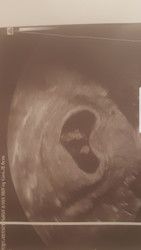

Hallo. Kann mir eventuell hier jemand erfahrenes helfen? Hab heut mein 1.Bild erhalten ohne großen Kommentar. Das Kind ist wohl das obere... aber was ist der Fleck weiter unten? Kennt sich jemand aus?

Vermutlich der Dottersack, von dem sich der Embryo "ernährt", bis die Plazenta das übernimmt.